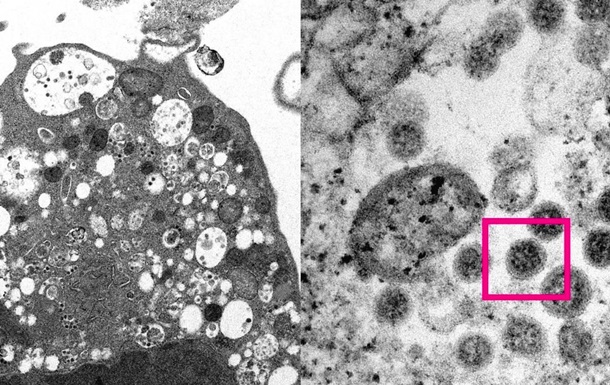

В результате эволюции штамм коронавируса Альфа начал вырабатывать больше белков, которые подавляют врожденную иммунную систему человека, говорится в публикации авторитетного научного журнала Nature. Схожие мутации есть у штаммов Дельта и Омикрон, сказано в статье.

Белки N, Orf6 и Orf9b нейтрализуют способность организма вырабатывать белки интерферона в ответ на попадание вируса внутрь.